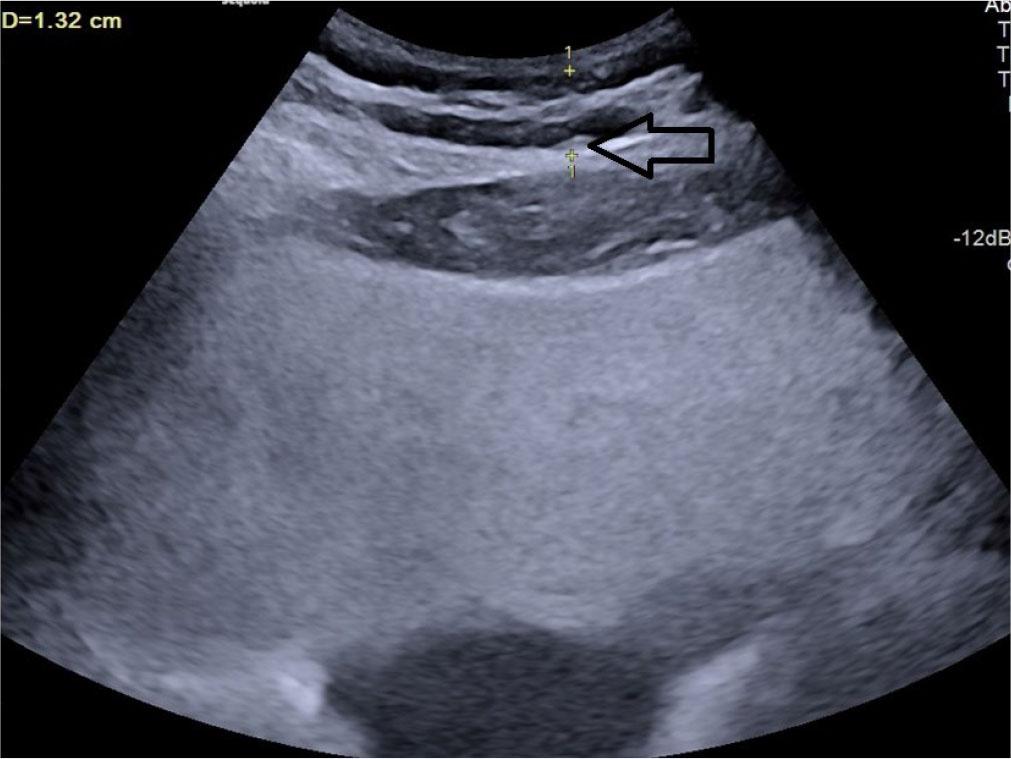

Posterior right perinephric fat thickness (PRPFT) – the maximum thickness of the fat layer located in the right posterior perinephric space, measured perpendicular to the renal capsule(20) (Fig. 1).

Longitudinal grey scale ultrasound showing measurement of posterior right perinephric fat thickness (PRPFT) denoted by calipers (arrow)